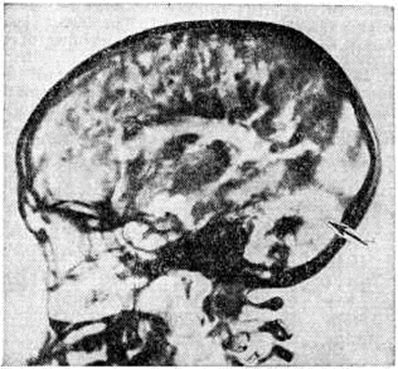

Рис. 4.

Пневмоэнцефалограмма при оливопонтоцеребеллярной атрофии: избыток воздуха в задней черепной ямке (указан стрелкой) свидетельствует об атрофии мозжечка.

Диагноз устанавливают с помощью пневмоэнцефалографического исследования (смотри полный свод знаний Пневмоэнцефалография), при котором отмечается повышенное скопление воздуха в задней черепной ямке (рисунок 4); менее постоянно расширение боковых желудочков, особенно их передних рогов, и скопление воздуха на месте атрофированных лобных долей. В целях диагностики может быть использована и компьютерная томография головы, которая при Оливопонтоцеребеллярная атрофия выявляет атрофию мозжечка, расширение околомостовой цистерны и иногда гидроцефалию.